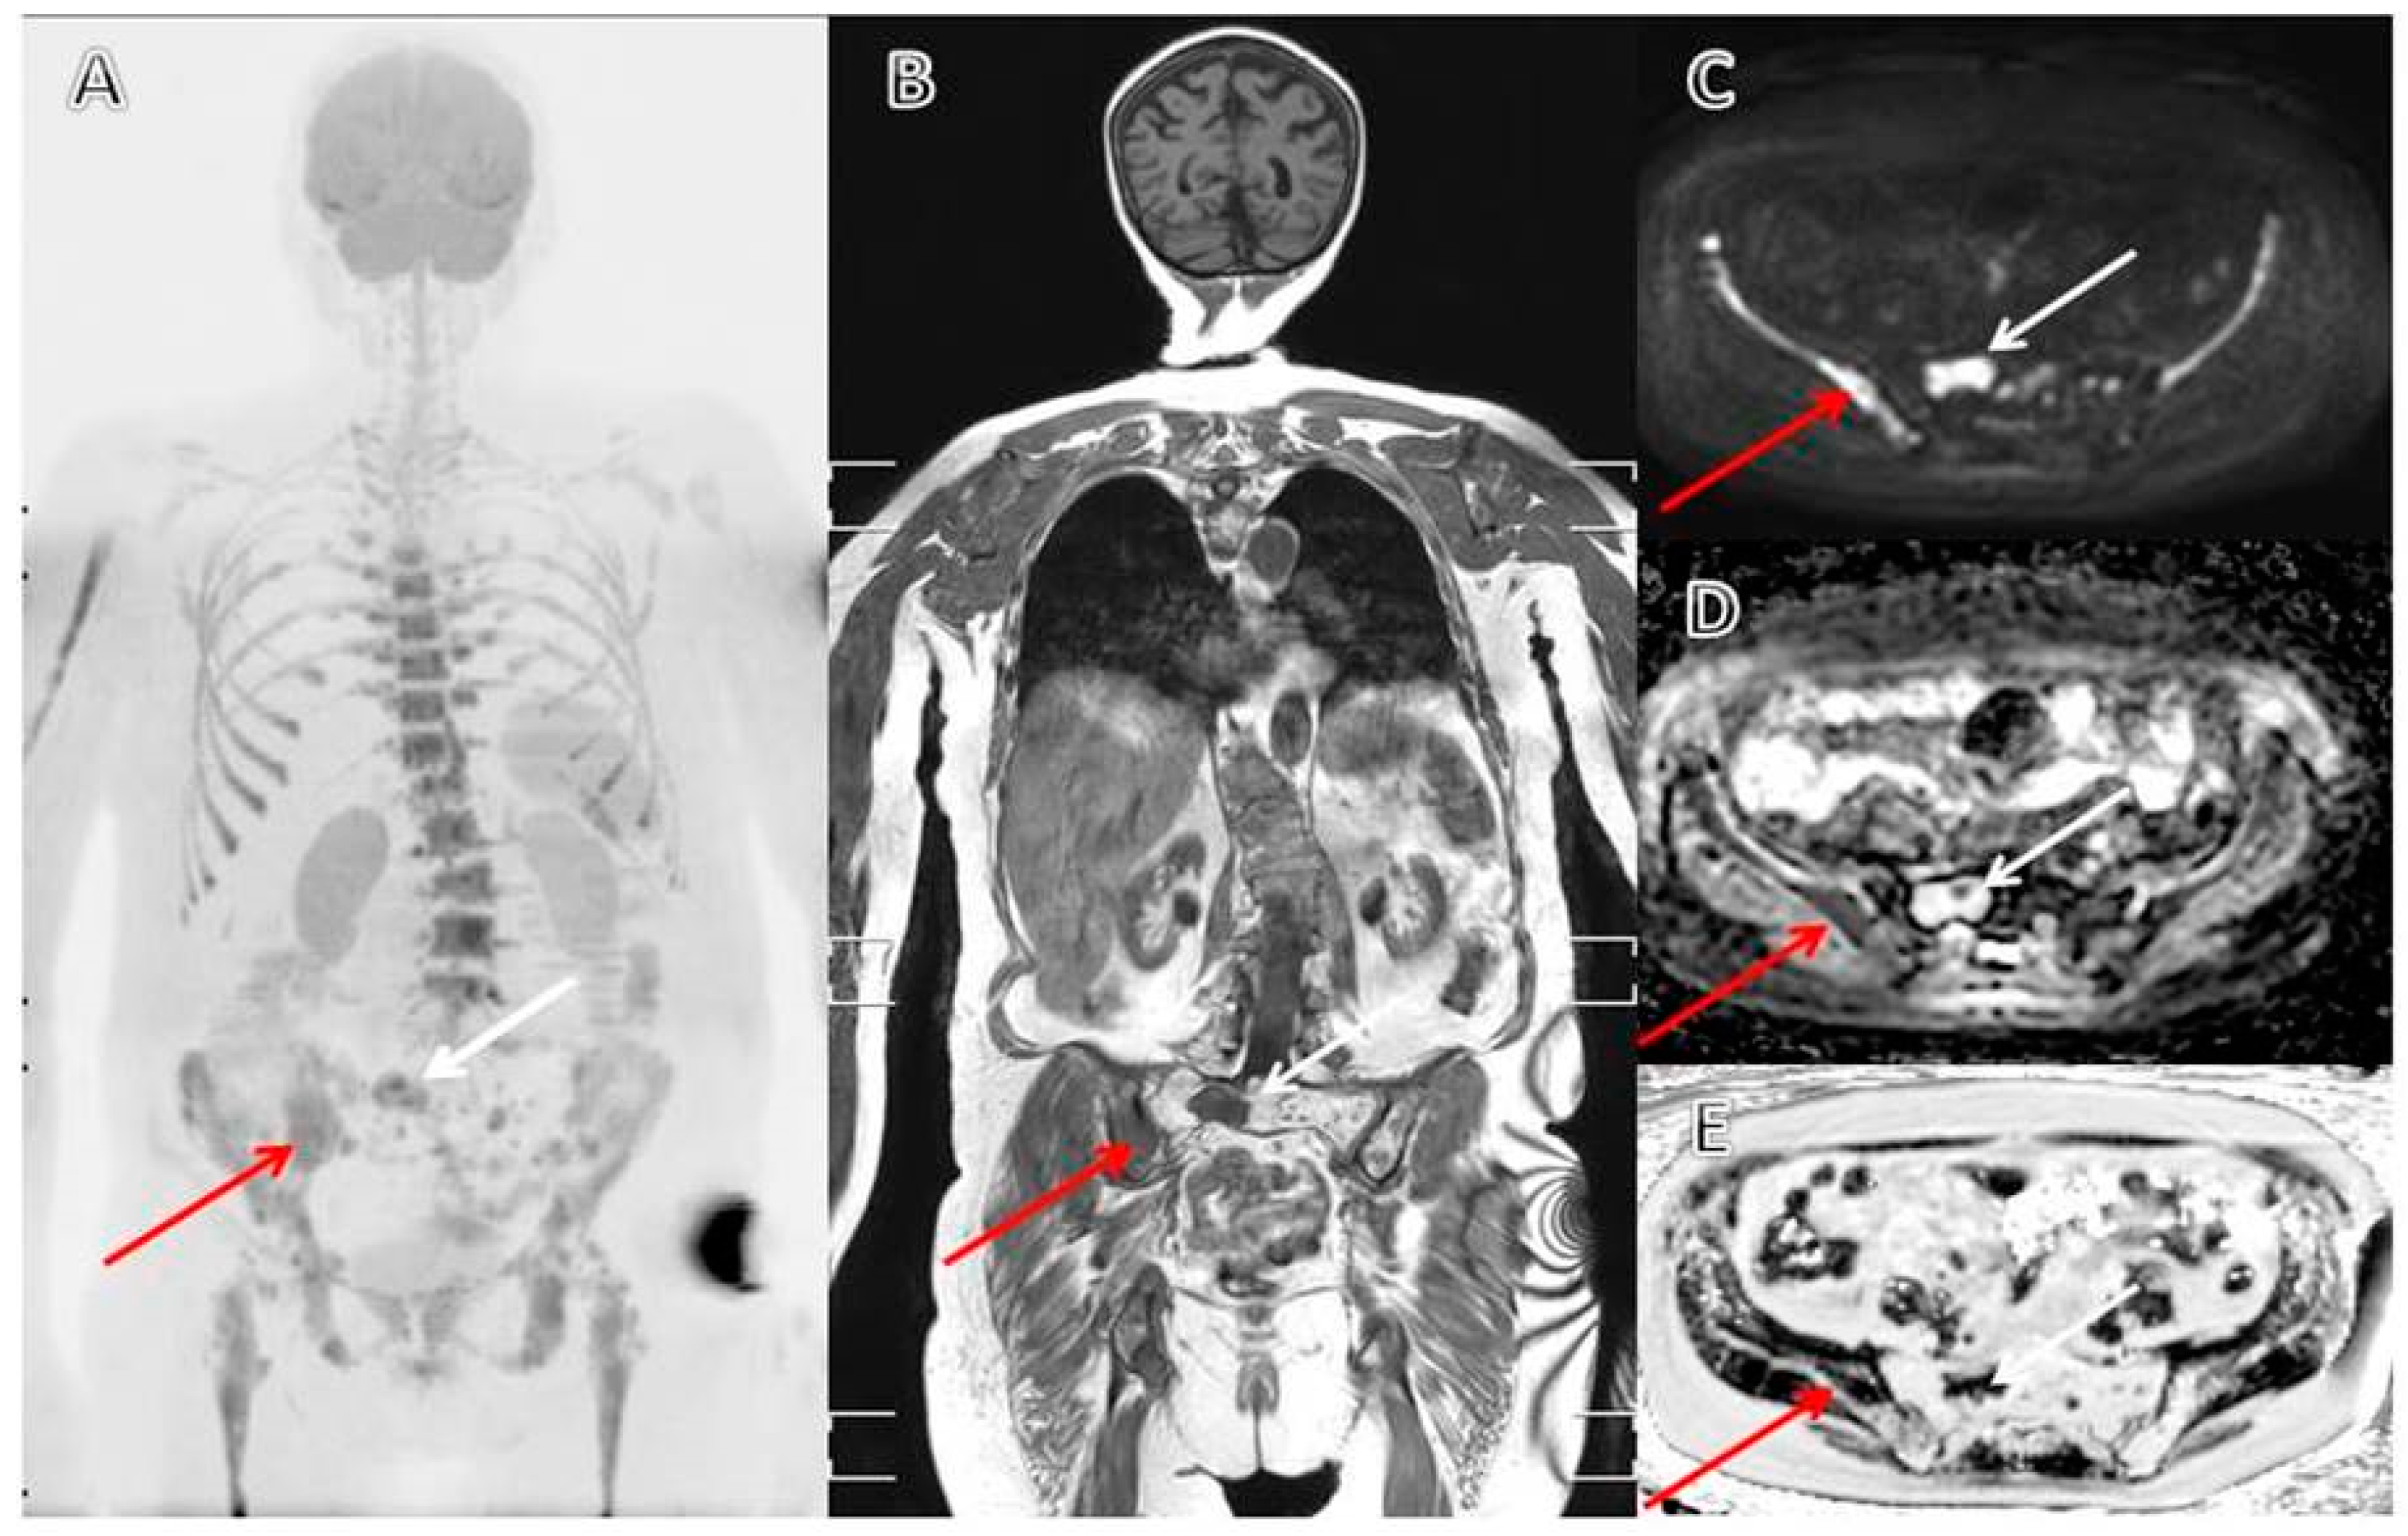

3.3. MRI as a Diagnostic and Prognostic Tool in Patients with Multiple Myeloma

3.4. The Evolving Role of FDG-PET/CT in Multiple Myeloma